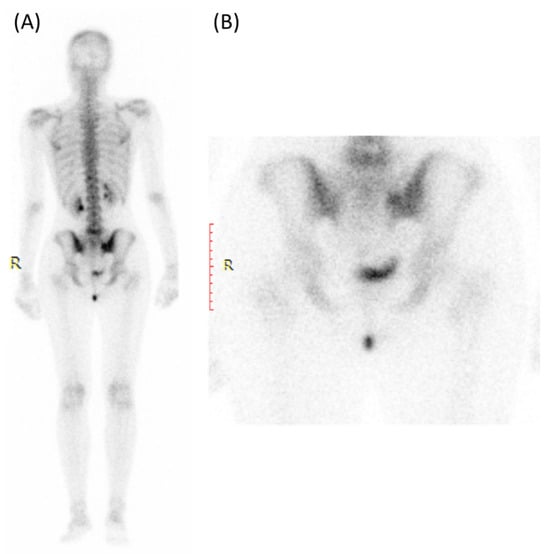

Nuclear medicine scans (bone scans) can also play a role in the evaluation of sacroiliitis, particularly in detecting active inflammation and assessing disease activity and inflammatory changes earlier than conventional X-rays [6,7].

Those scans can show the extent of inflammation and involvement of multiple joints in cases of spondyloarthritis [62]. Bone scans can provide a whole-body assessment, which is valuable for identifying other areas of inflammation or disease activity in conditions like ankylosing spondylitis [62].

As provided in Figure 8, one of the most commonly used nuclear medicine scans for sacroiliitis is the Technetium-99m bone scan [6]. This tracer is taken up by bone tissue in areas of increased metabolic activity [6]. In sacroiliitis, areas of active inflammation and increased bone turnover will absorb more of the radioactive tracer, leading to “hot spots” on the scan [63]. A bone scan can provide information about the extent and distribution of inflammation in the sacroiliac joints and other areas of the body, if applicable [64]. It is particularly useful for detecting active inflammation and assessing the overall disease activity in sacroiliitis [6].

Figure 8.

Bone scan (using Tc99m HDP) for a 30-year-old female presented with Lt hip pain showing focal increased tracer uptake in the Lt sacroiliac joint in the blood pool (A) and delayed images (B).